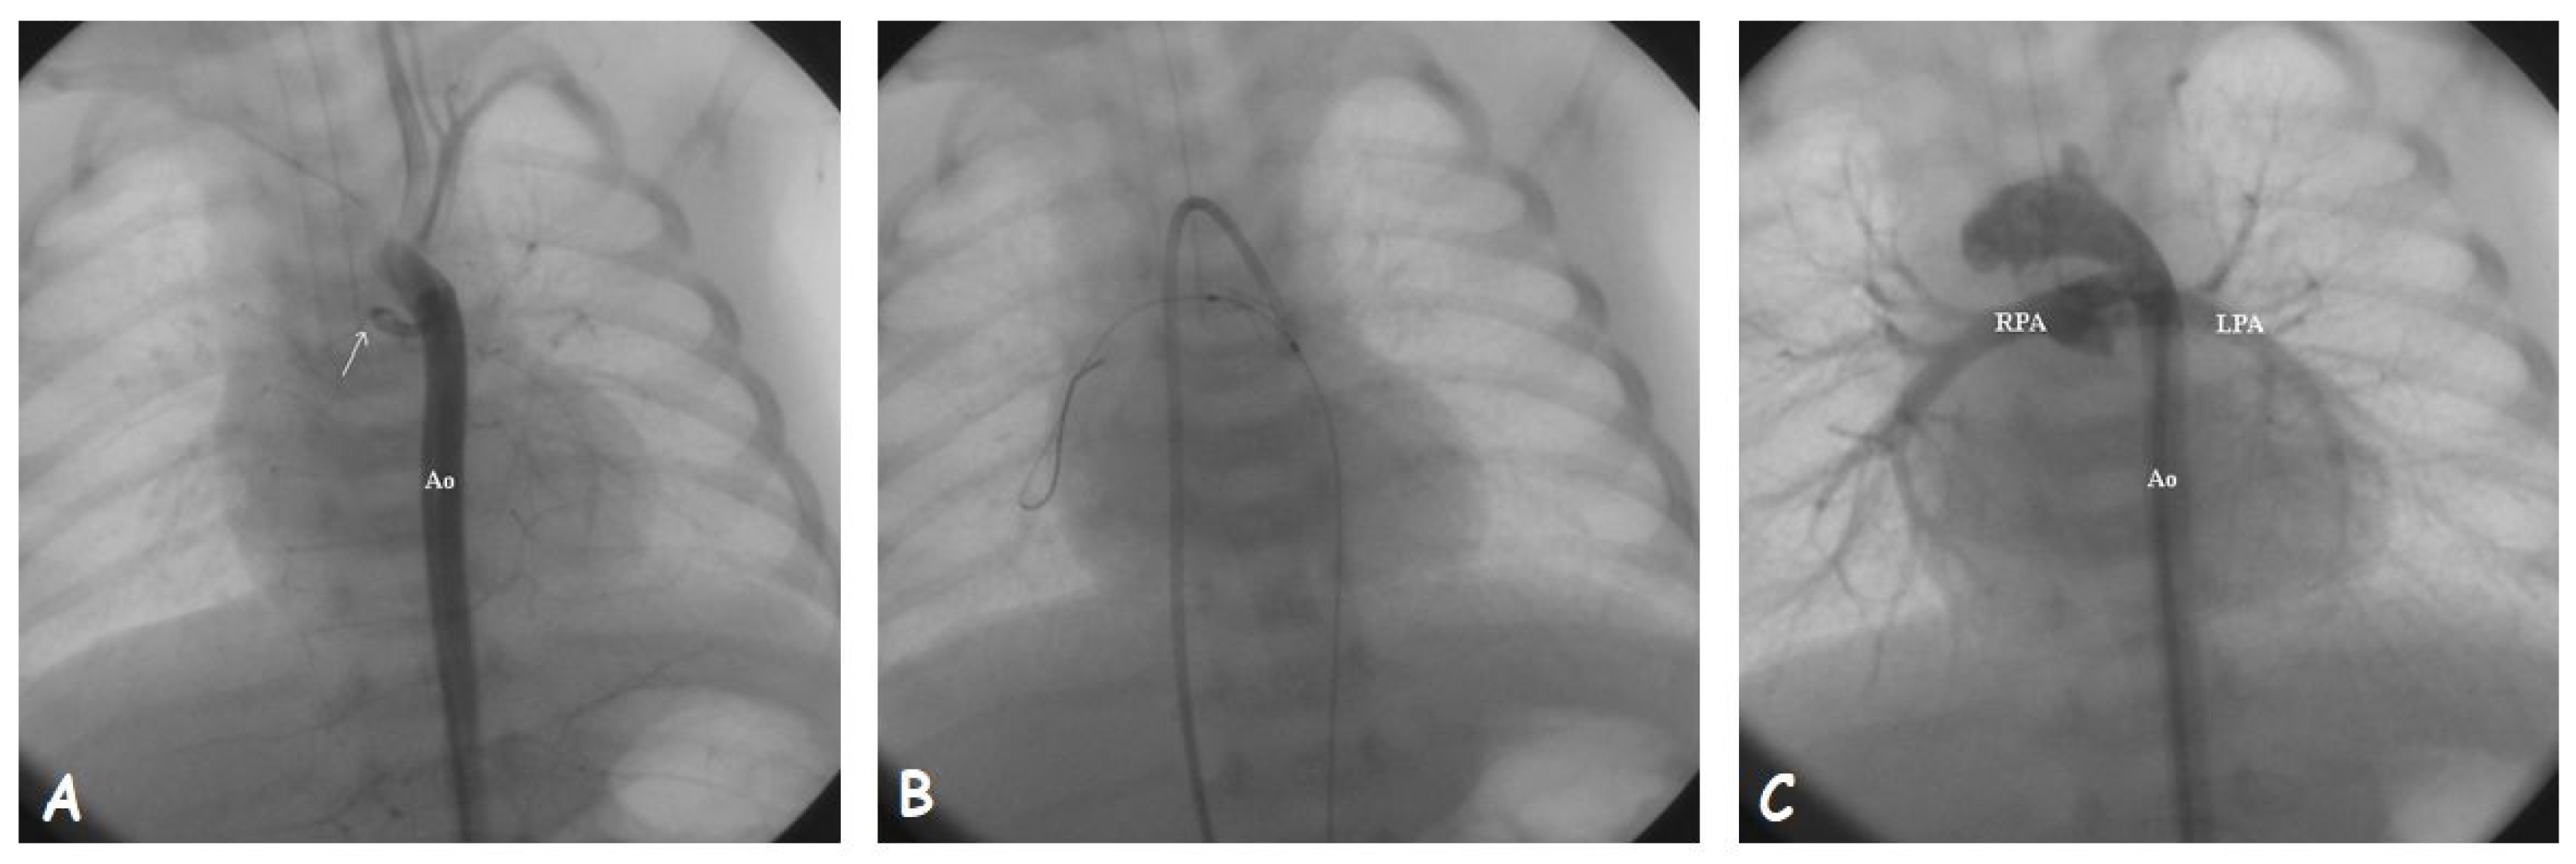

1.6. Procedural Technique: AD Stenting